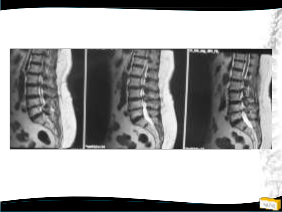

Olgu

• 64y, K

• Bel ve her iki bacak ağrısı

• NM normal

Yapılan Ameliyat: L1-L5 dekompesyon + transpediküler stabilizasyon